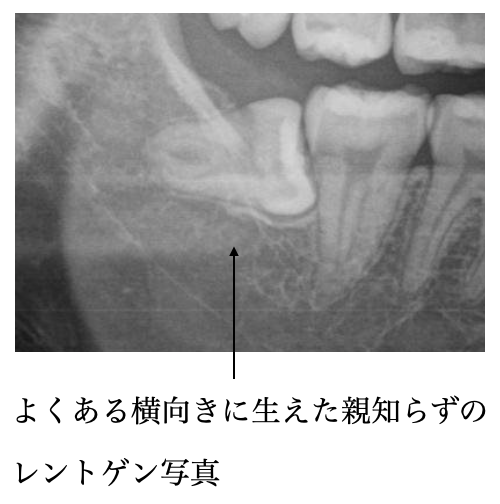

トラブルが起こりやすい親知らずの生え方

❶完全に放出している親知らず

❷歯茎から一部でている親知らず

この2つの生え方の人は特に要注意!

これらの生え方の場合、親知らずはお口の中でもとても奥にある歯なので、磨きにくいことが多く、清掃不良になやすく、清掃不調が原因でとトラブルがよく起こるのです。